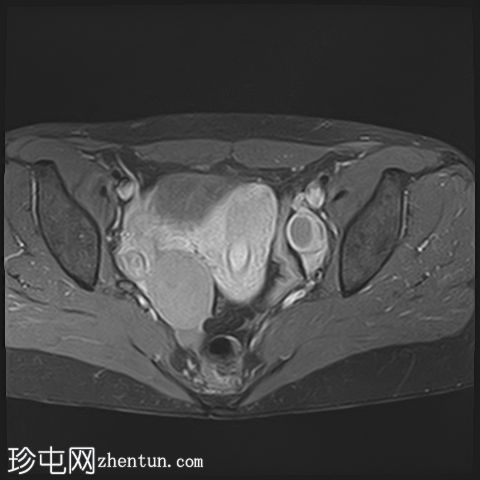

冠状位

T1

已确诊3例卵巢囊肿:

右侧卵巢出血性囊肿,T1成像呈中等信号,T2成像呈高信号,伴有薄内部分隔

左侧卵巢出血性囊肿,信号特征与右侧囊肿相似

左侧单纯性卵巢旁囊肿,T1成像呈低信号,T2成像呈高信号

此外,所有囊肿均未显示弥散受限或实性成分强化。

所有囊肿均仅显示薄层外周壁强化。

道格拉斯囊右侧可见轻度积液。

本例卵巢囊肿呈中等 T1 信号,类似于肌肉信号,T2 信号高,伴有薄内隔和外周壁强化。但无内部强化或弥散受限。STIR 序列显示与 T2 一致的信号,无任何脂肪成分。该表现提示卵巢出血性囊肿处于早期或消退期。

此外,左侧卵巢旁囊肿外观简单,T1 信号低,T2 信号高。